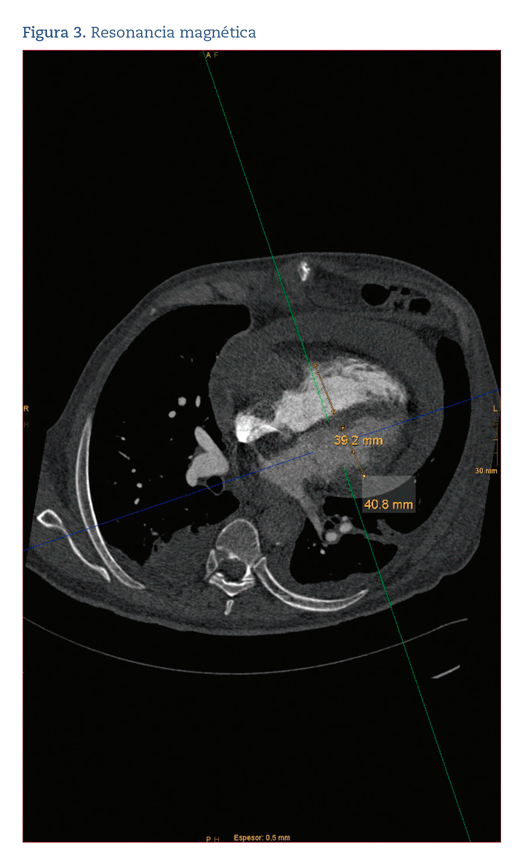

En la analítica, destaca un dímero D de 2322 ng/mL (normalidad: 0-500). Se realiza una angiografía por tomografía computarizada (angio-TC) de arterias pulmonares que descarta TEP, pero en la que se observa un marcado derrame pericárdico y una masa cardíaca de 70x35 mm en la aurícula derecha, que se confirma con un ecocardiograma. El paciente ingresa en la planta de cardiología y se continúa el estudio con una resonancia magnética (RM) en la que se aprecia que la masa infiltra la pared libre de la aurícula derecha con invasión del pericardio visceral (figura 3). Durante la realización de dicha prueba el paciente presenta deterioro clínico con hipotensión, por lo que, ante la sospecha de taponamiento cardíaco, ingresa en la unidad coronaria, donde se le realiza una pericardiocentesis urgente, obteniéndose 1 litro de líquido hemorrágico con anatomía patológica negativa para células tumorales. Más tarde se completa el estudio con una tomografía computarizada (TC) toraco-abdomino-pélvica en la que se observa una lesión expansiva (LE) sólida, hipocaptante en el segmento 6 del hígado, sugestiva de metástasis, que en la tomografía por emisión de positrones (PET)-TC no presenta significado patológico y se repite la RM cardíaca que muestra una masa sugestiva de angiosarcoma. Se realiza una punción con aspiración de aguja fina (PAAF) de la LE hepática que, con técnicas de inmunocitoquímica, resulta positiva para los marcadores CD34 y CD31, compatible con angiosarcoma.